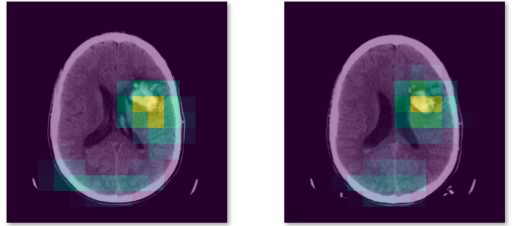

如果想更花哨一点,可以用机制来找病变。最后的效果就是:输入一张医学图片,它会输出这张图中患病的概率,并且把这张图中的病变突出显示出来。

开源数据集:CQ500